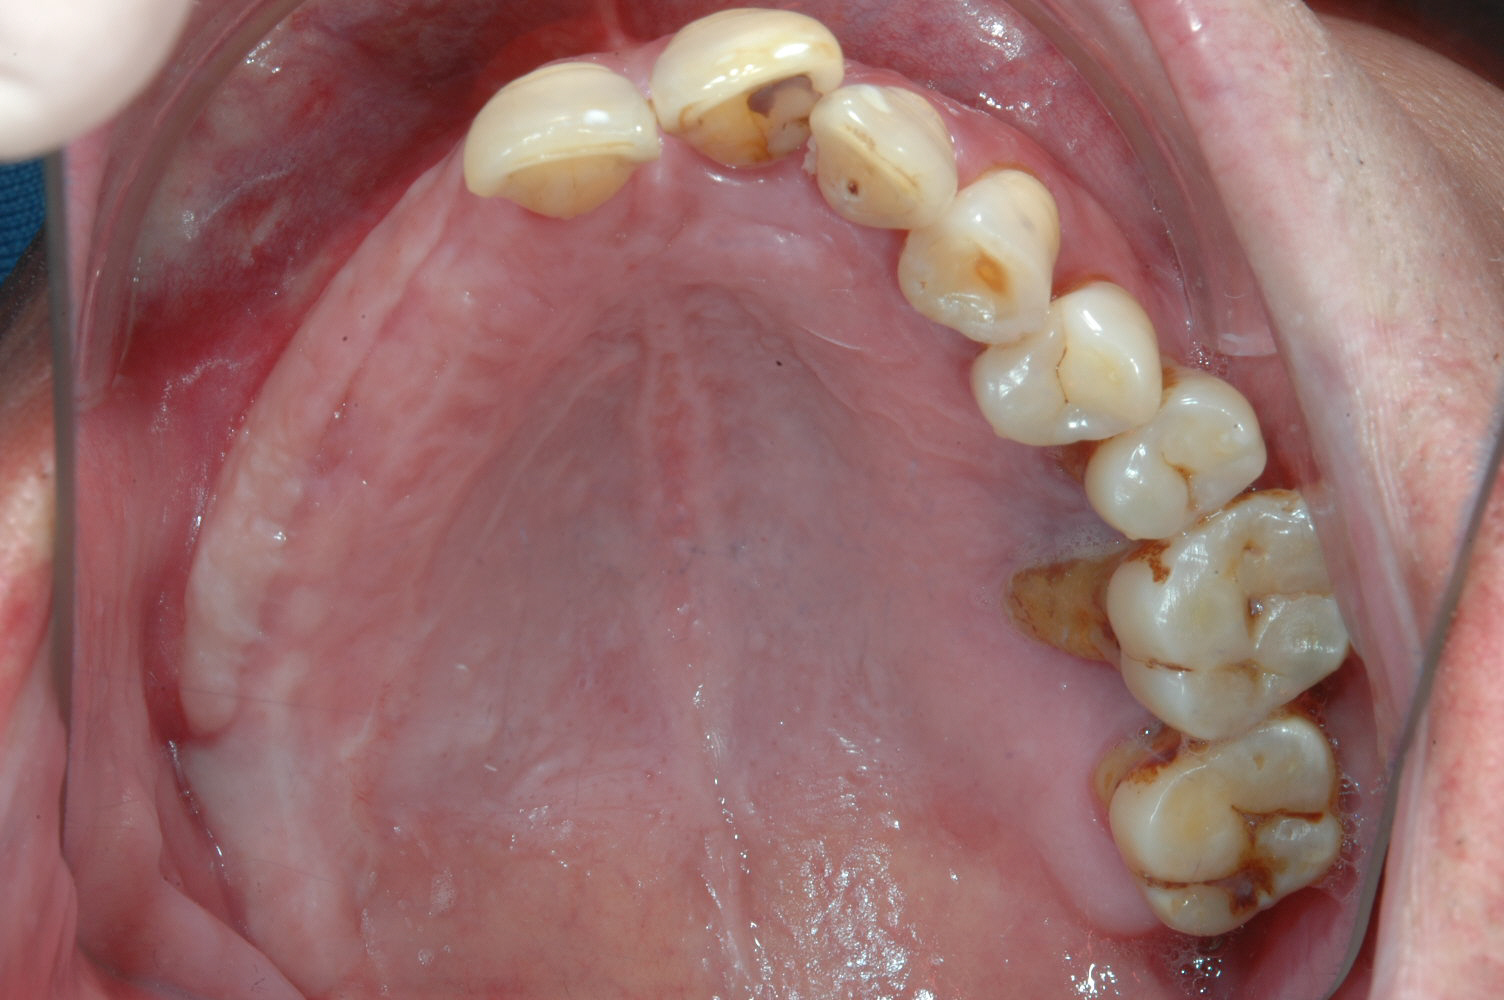

牙齦移植術(補肉)

利用自體牙齦組織移植至牙齦萎縮處或是角質化牙齦不足的地方,恢復牙齦美觀與健康,以利未來植牙提供穩定的牙周環境。